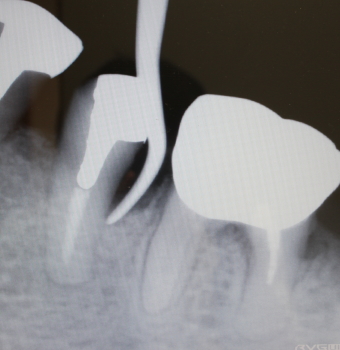

35番遠心より排膿

同部のX-ray